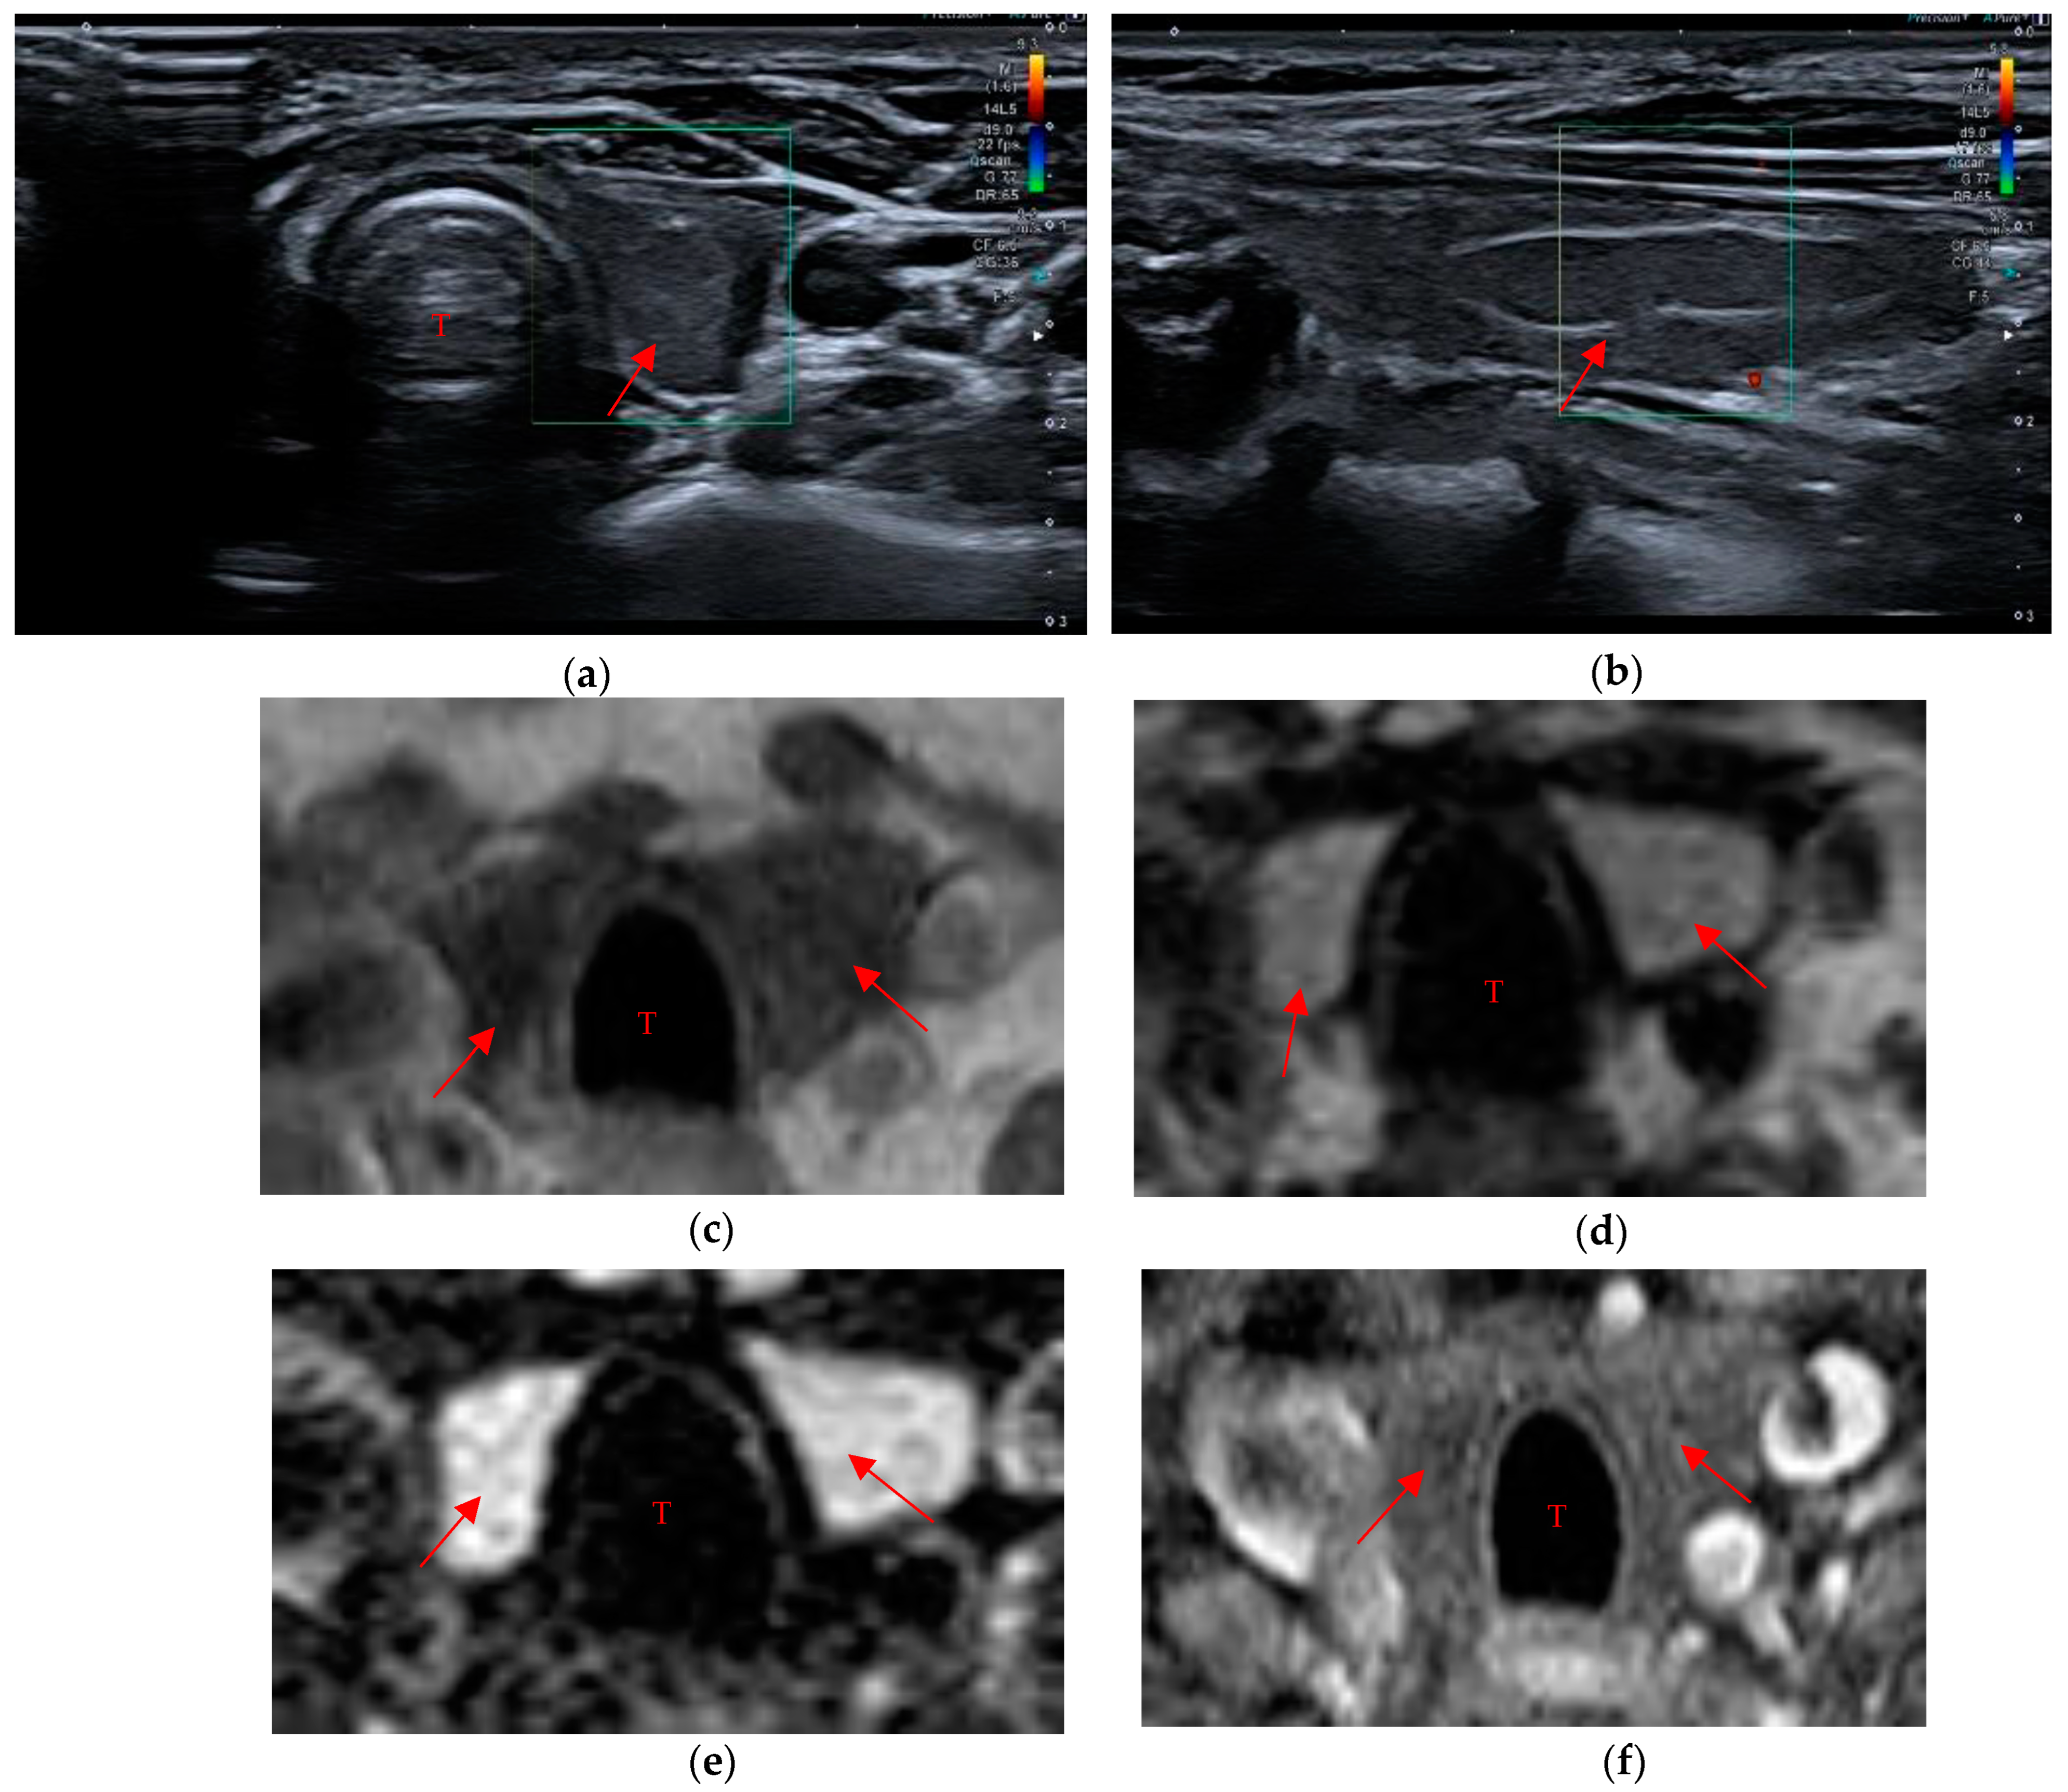

Data in the literature concerning the biocompatibility, the tolerability and the time resorption of these hemostatic agents are few [22,23,24,25,26]. Our study showed a longer resorption time than the data provided by the producers (7–14 days with regard to the oxidized and regenerated cellulose-based hemostatic; the failure rate for absorption is not clearly specified by the manufacturers). Therefore, it is important to keep in mind that failure or delay in the reabsorption of the hemostatic material can cause diagnostic mistakes that affect the patient’s therapeutic path. In fact, some of the patients had already undergone further diagnostic investigations before being enrolled in the study, such as scintigraphy and ultrasound-guided needle aspiration for residual material in the thyroid space in order to exclude a neoplastic recurrence. In particular, seven of these patients were subjected to strict ultrasound surveillance (three-month follow-up), one patient to MRI and three patients to scintigraphic evaluation that showed no areas of significant radiopertechnetate uptake and was negative for residual thyroid tissue in the anatomical loggia (Figure 5a–f). One of the last three patients had also undergone a needle aspiration evaluation that confirmed the presence of the hemostatic, described by the pathologist as “amorphous inorganic material referable to surgical sponge” (a similar case is described by Kurian E.M. et al., in which the patient, during follow-up after lung resection for carcinoma, underwent endobronchial ultrasound-guided transbronchial needle aspiration on suspicion of lymph node metastasis, but the cytological examination showed the presence of foreign material, later proven to be the Surgicel® placed during surgery) [27,28]. Lastly, in two other patients, although they were not subjected to further diagnostic investigations, the presence of the swab was misinterpreted as post-surgical native thyroid residue. These examples make it clear how diagnostic mistakes cause unpleasant consequences for the patient’s diagnostic–therapeutic path and increase the clinical management cost.

Figure 5. “Thyroid-like” shape of the residual swab (red arrow in the imagines) in a patient who underwent thyroidectomy. (a,b) The mildly hypoechoic pattern is recognized during ultrasound evaluation. (ce) The swab in MR images appears moderately hypointense in T1w sequences and relatively hyperintense in T2 and in fat-suppressed T2. (f) No enhancement is seen in the post-contrast sequences, unlike what would occur in the native thyroid. Trachea (T).